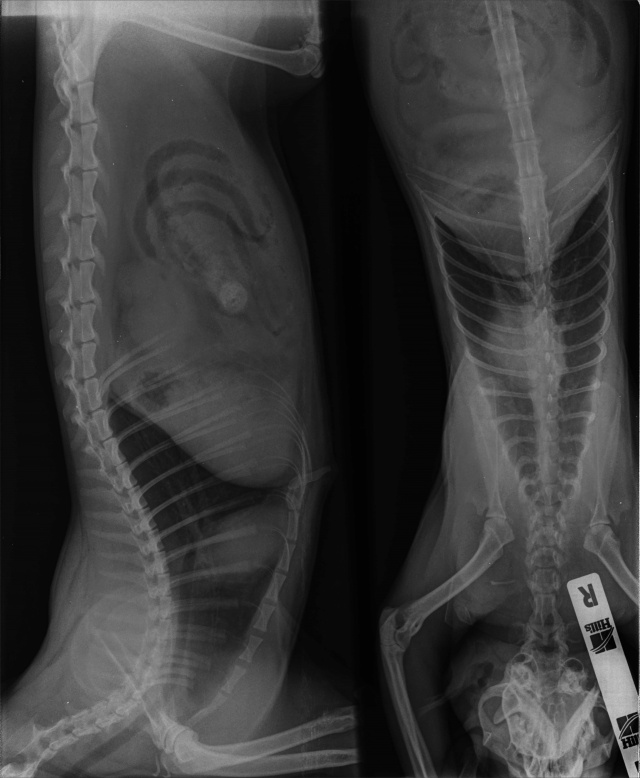

- Множественный оскольчатый перелом бедра

На 26.11.2014 коту проведена операция по восстановлению мочевого пузыря и устранению перитонита и разрыва с отрывом.

27.11.2014 - остеосинтез бедренной кости.